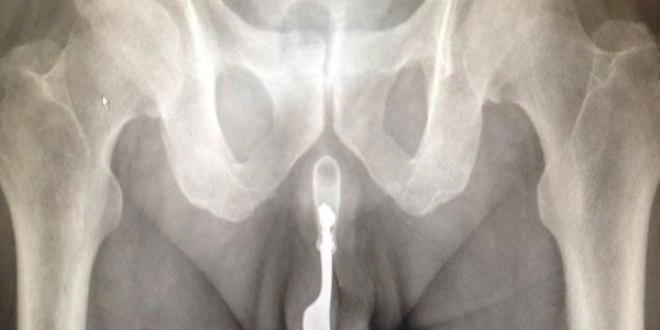

Selon l'article "An unusual urethral foreign body" ("Un corps étranger inhabituel dans l'urètre"), publié dans l'International Journal of Surgery, l'homme de 70 ans s'est présenté aux Urgences de l'hôpital de Canberra avec un pénis en sang, "après s'être introduit une fourchette dans l'urètre pour stimuler le plaisir sexuel".

L'homme avait introduit la fourchette de 10 cm, en métal, douze heures auparavant, mais ne parvenait plus à la retirer, poursuit l'article, qui ne précise pas la date des faits.

Les docteurs, confrontés pour la première fois à un cas pareil, "ont discuté de plusieurs opérations possibles", avant de retirer l'objet avec un forceps et beaucoup de lubrifiant, alors que le patient était sous anesthésie générale.